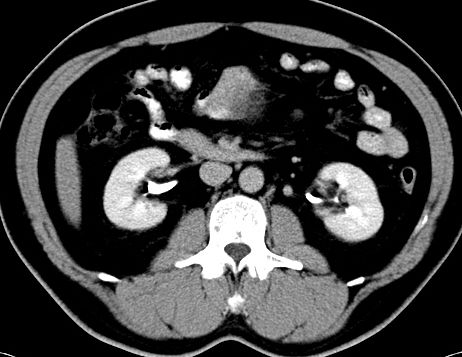

(腹腔)神经鞘瘤

男,48岁,间断性下腹不适1年。

手术探查

:距回盲部28厘米处肠系膜根部可见5*7cm左右包块,质中等硬度,活动度尚可,肝、胆、胰、脾肾未见明显异常。

病理

:(腹腔)

神经鞘瘤

,伴出血、坏死及囊性变,伴淋巴结反应性增生。

免疫组化结果

:sma(-), desmin(-), cd117(-), s-100(+++), nf(-),vimentin(+++).